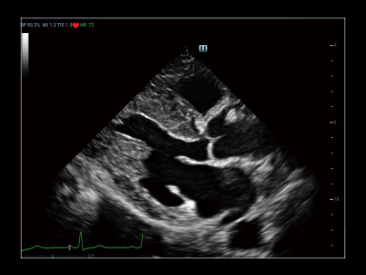

Wyra?niejszy obraz umo?liwiaj?cy pewn? diagnoz?

iClear+ jest oparty na wydajnej technologii przetwarzania ZST+ i zapewnia lepszy stosunek sygna?u do szumu (SNR) oraz mniej zak?óceń, co pozwala na lepsz? wizualizacj?.